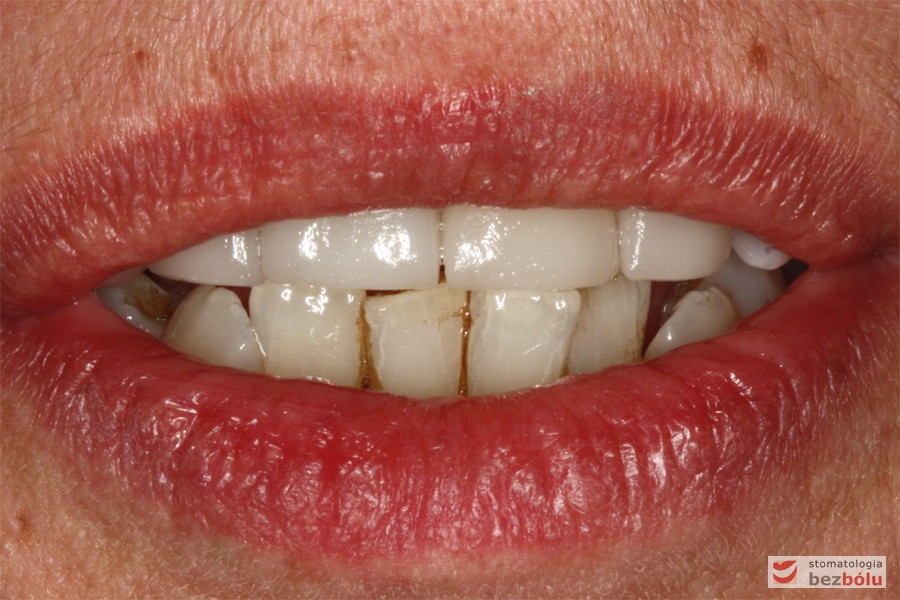

Usta w średnim uśmiechu - trójkątne przestrzenie między zębami w szczęce

Usta w średnim uśmiechu – trójkątne przestrzenie między zębami w szczęce